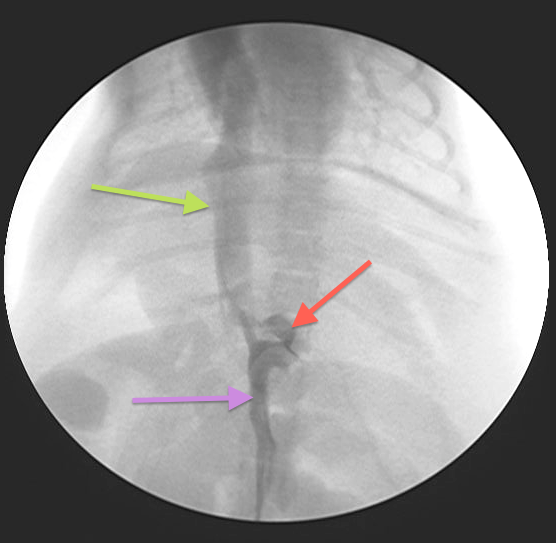

Intraoperative fluoroscopy is used to confirm the presence of a shunt

Fig 2: PSS surgery is performed using intraoperative fluoroscopy

Fig 3:

Intraoperative fluoroscopy (portovenogram) showing the same PSS as in Fig 1: Purple arrow = Portal vein; Green arrow = CVC; Red arrow = PSS